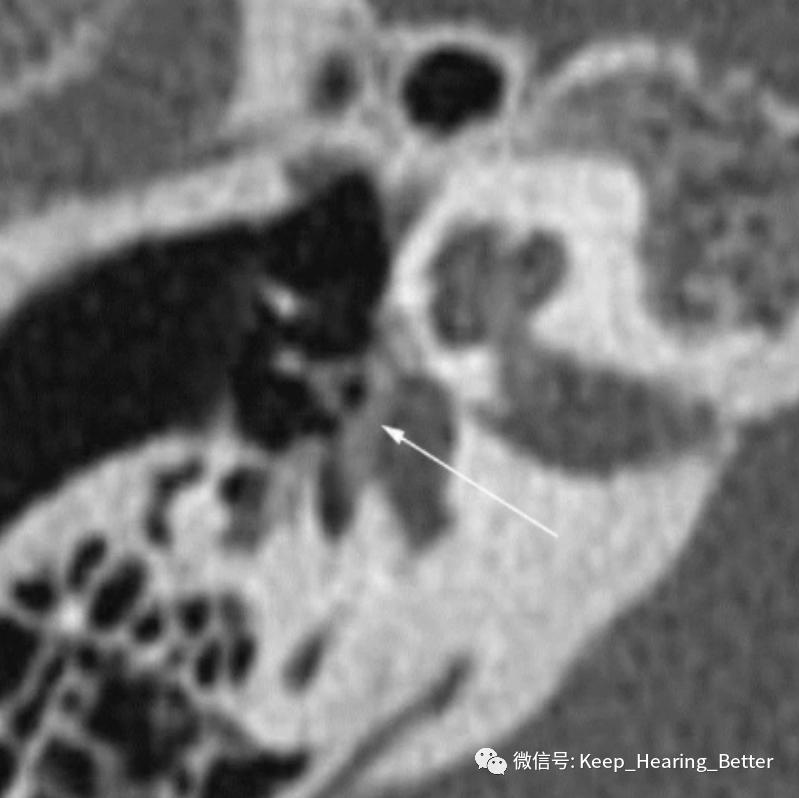

典型案例CT可见骨质疏松的双环征(如下图椭圆标记)、卵圆窗附近硬化灶(如下图箭头)等。